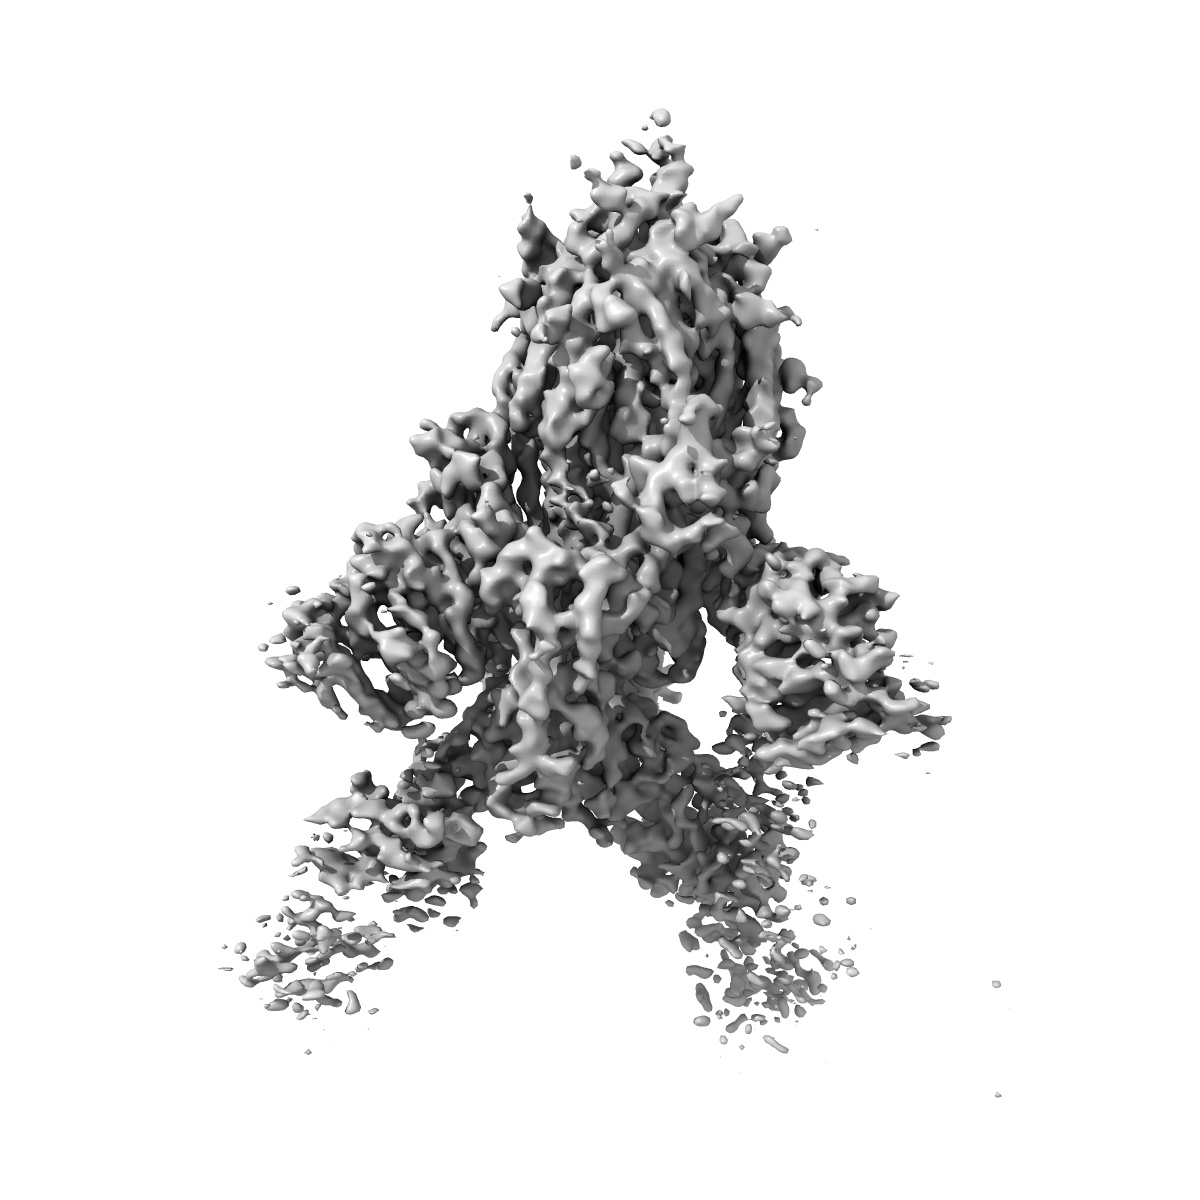

Structure of the SARS-CoV-2 S 6P trimer in complex with the human neutralizing antibody Fab fragment, BG1-24

Single-particle4.0 Å

Sample: Ternary complex of BG1-24 Fab bound to SARS-CoV-2 spike trimer